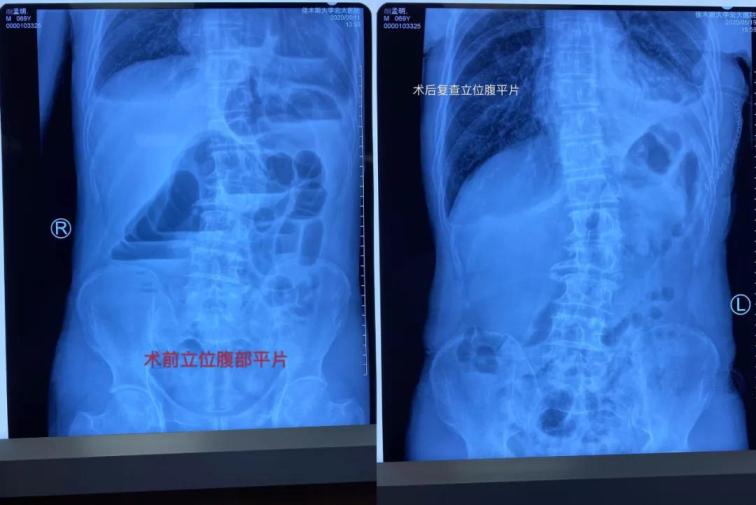

患者顏某某,男,69歲,因“間斷性腹痛腹脹、惡心嘔吐肛門(mén)停止排氣排便4天”于5月11日17時(shí)22分經(jīng)門(mén)診掛號(hào)診療,以“腸梗阻”收住我院普外一科。主管醫(yī)生張志光詳細(xì)詢(xún)問(wèn)患者病史、全面查體,結(jié)合相關(guān)輔助檢查,入院給予禁食水、胃腸減壓和補(bǔ)液治療。

雖然患者表現(xiàn)為腸梗阻癥狀,但是從事普外多年、細(xì)心的張醫(yī)生對(duì)患者的胸部CT心前區(qū)顯示低密度影像產(chǎn)生疑問(wèn),懷疑膈疝可能,并于5月12日晨找胸外科周鋼主任會(huì)診。 周鋼主任結(jié)合病史、癥狀、查體、輔助檢查,高度懷疑膈疝中的心膈角疝,疝內(nèi)容物考慮結(jié)腸可能,因患者目前表現(xiàn)為腸梗阻,腸管卡壓時(shí)間長(zhǎng)易導(dǎo)致壞死,且胸部CT表現(xiàn)心包填塞,此時(shí)動(dòng)脈血壓已經(jīng)下降,靜脈血壓升高,脈壓差縮小,已經(jīng)出現(xiàn)休克。

術(shù)中發(fā)現(xiàn)橫結(jié)腸疝入心包并嵌頓,腸管高度擴(kuò)張,已經(jīng)顏色較暗,同時(shí)疝入心包腔內(nèi)還有大網(wǎng)膜,已表現(xiàn)血運(yùn)障礙。心臟嚴(yán)重受壓,近乎停止跳動(dòng)。緊急切開(kāi)擴(kuò)大疝環(huán),觀察疝入的腸管和大網(wǎng)膜血運(yùn)情況,約觀察30分鐘血運(yùn)障礙恢復(fù)后,小心將疝入的腸管和大網(wǎng)膜還納入腹腔。心包腔恢復(fù)原有空間,心臟開(kāi)始恢復(fù)節(jié)律性跳動(dòng)。術(shù)后病人轉(zhuǎn)入胸外科病房,監(jiān)護(hù)綜合治療護(hù)理,目前患者恢復(fù)良好。